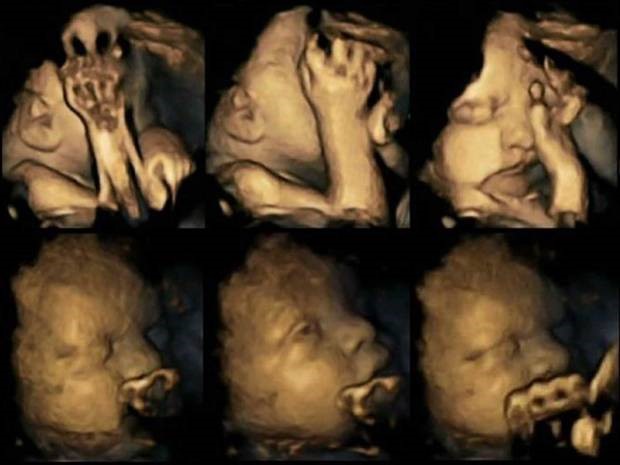

Притеснителните резултати от ултразвука, които специалистите анализирали, доказват, че при ембриони на майки, които пушат движението на ръцете и устата се увеличават драстично. Това пък е сигурен знак за проблем в развитието на централната нервна система на бебето.

Изследванията показали завишено движение при ембрионите, носени от майки, които пушат. Обикновено бебетата движат устата и ръцете си, но тези движения значително намаляват при наближаване на раждането, тъй като ембрионът започва да се развива и да има все по-голям контрол над моторните си функции.

Учените предполагат, че това се дължи на факта, че никотинът забавя развитието на централната нервна система на детето, която контролира движенията му.